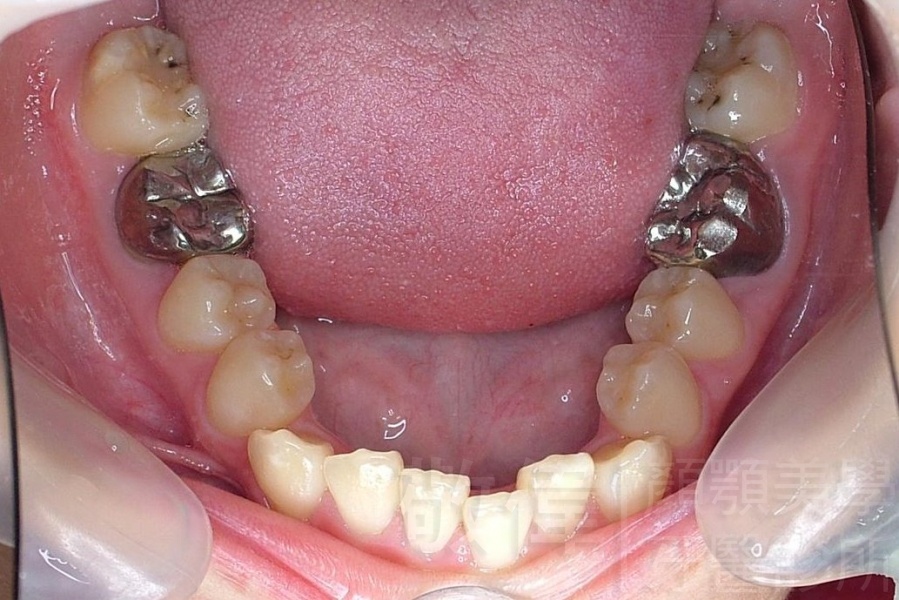

齒顏矯正/戽斗、亂牙、爛牙,變身 免植牙的健牙美女

<個案說明>

變臉矯正,原來戽斗妹跟大歪臉變成自信正妹

經由本院3D數影X光影像儀分析、與3D齒顎顏矯正技術,再配合口腔顎面正顎專科醫師施以正顎手術治療,雙方共同合作,使患者臉部外觀有很好的改善,大歪變小歪,產生了天南地北的大改變,她的人生也整個變得不一樣。

因為矯正與正顎手術的配合,使「戽斗妹」變成了「陽光正妹」,完全的改變了她的人生,在面對各種場合、與人交際都散發出自信微笑。所以,奉勸家長,如果小朋友有臉顎畸型的問題,應該考慮配合做這種簡單、安全、有效的正顎手術。